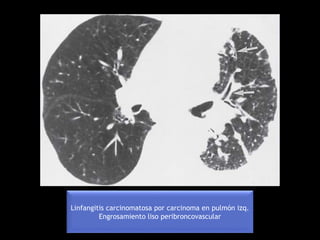

Linfangitis carcinomatosa por carcinoma en pulmón izq.

Engrosamiento liso peribroncovascular